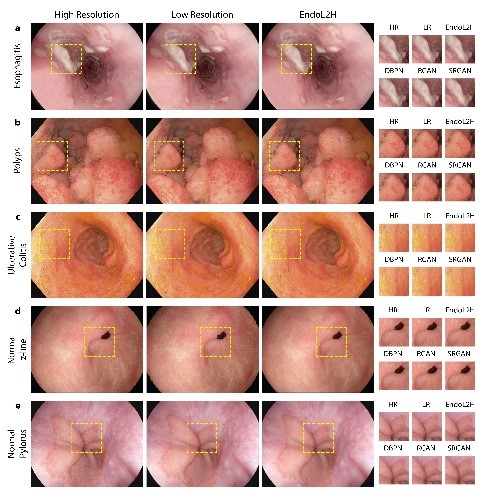

- Computational Imaging Laboratory

https://bme.bogazici.edu.tr/en/computational-imaging-laboratory

Field of Study: Magnetic resonance imaging techniques (MR spectroscopic imaging (MRSI), arterial spindle labelling (ASL), diffusion tensor imaging (DTI), etc.) are used to identify anatomical, physiological and biochemical changes due to brain diseases, classification of medical image data for disease diagnosis using machine learning and deep learning methods, and image enhancement (super enhancement).To identify anatomical, physiological and biochemical changes due to brain diseases using magnetic resonance imaging techniques (MRI), classification of medical image data for disease diagnosis using machine learning and deep learning methods and image enhancement (super resolution), to accelerate routine MRSG techniques used in the clinic, To develop quantitative molecular MR imaging techniques for more sensitive and accurate data acquisition and processing, to develop modelling and analysis methods to create MR parametric maps, to develop user-friendly data analysis interfaces, and to produce phantoms that mimic brain chemistry and anomalies.